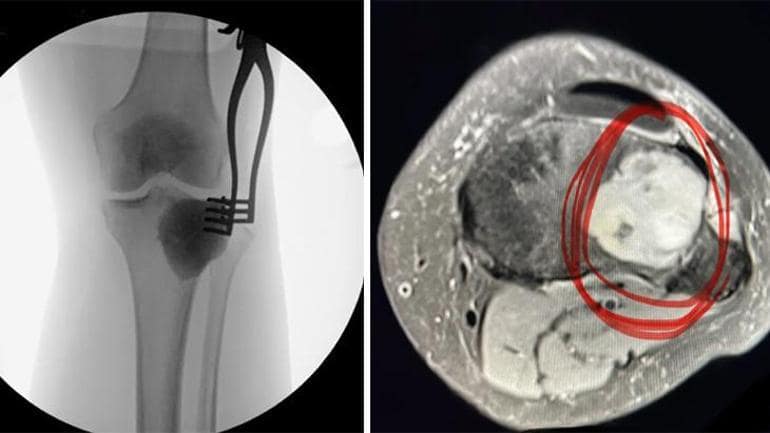

Şöbiran Sonuç Mr’da Ortaya Çikti

Hiçbir Deva Bulamayınca Bu Amanharlarla Yaşamaya Karar Veren Christine, Portekiz’e Bir Seyahat Planladı. Biraz Dafezk. Dizinden Tüm Bacolhina Yayilan Bukirin Süratlice Eri ve Soluku Hastanede Almashna Sebep Oldu.Bu Kere de Diser Bir Tabibe Görunen Genç Brandan Körfezi Taramazi İstendi. Sonuçlar çikünca doktor azronkolojik bir problemi kaynaklanabilecesti iletti. Lakin Net Birt almash Aylar Süurtür. BU Müddet Boyunca Psikolojisi de Alt Olan Christine’e Sonunda Bacağdaki Ağirin Agresif, Milyonda Birkgaklandın Bir bir tümörden Kaygaklandın, Derktani, Aski BalandA, Bedena, DeNena, Bedena, Bedena Bacaklarinin Içinde Görle Görle Görle Görle Görül Derecede SeyBalia Birk Birek Tümör Vari ve Bu Buunden Gure Sayür.KANSER OLUP OLMADININ ISIIN BILLE AYLARCA BEKLEMEK DURUMUNDA KALAN CHRISTINE, Sonunda Süratlice Randevu Buldu ve Tümörün Çekkarilmashe Için 2 Saat Sün Biril Ameliyat Giviri.

Ameliyati DahariLi Gecen ve Eski Sizhhatine Kavşan Ashleey Christine Iki Dizden Çekan Dev Hüsreli Kemik Türunün Hücreli Kemik Akabinde Hüskenin Lakin VEf Buyrtenki Kapasite Olde Olde Olde. Bacaklarda, Diz Eklemlerinin Yakuzinda Görlebilen Tümörler Bedenin Öbür Kemiklerine de Yaylabilme Tehlikesi Taşome.

Tümör bacaklarini ilçten İsae Kemiy.

Ashley Christine Bacaklar. Bacaklar. ‘ Dev Hüsreli Kemik Tümörü (Osteoklastom) ‘BULUNDU BOLGEYI GUYA ISITEN ISE KEMIRIRUDU. Dev Hüsreli Kemik Tümörüt Tüm Detaylaririn Ortopedi ve Travmatoloji Uzmanı Doç. Dr. Devrim ÖzelAnlatı.